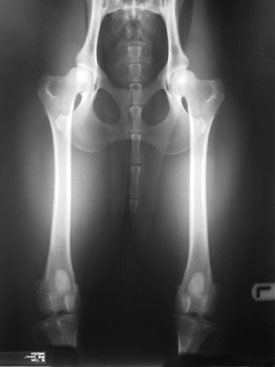

Heupdysplasie en elleboogdysplasie zijn vervelende en pijnlijke aandoeningen die bij verschillende hondenrassen voorkomen. Om te zorgen dat we gezonde honden hebben moeten we alleen fokken met ouderdieren die gezond zijn en vrij zijn van deze erfelijke ziekten. Daarvoor is het erg belangrijk om deze ouderdieren te onderzoeken op heup- en elleboogdysplasie door middel van een officieel röntgenonderzoek.

Op de dag van het onderzoek dient u uw hond nuchter te houden. In de meeste gevallen zal de hond gesedeerd (dat is een lichte narcose) moeten worden voor het maken van de foto’s. Deze moeten namelijk van hoge kwaliteit zijn. Daarvoor moet de hond exact in positie worden geplaatst en mag deze niet tegenstribbelen. Foto’s die niet aan de eisen voldoen worden niet beoordeeld door het beoordelingspanel van de Raad van Beheer en moeten opnieuw worden gemaakt.

Voor het HD-onderzoek moet 1 foto worden ingezonden, voor het ED onderzoek 4 of 8 opnames.

We kunnen vaak op vroege leeftijd met een röntgenfoto reeds vaststellen of een hond lijdende is aan HD of ED, maar voor een officiële beoordeling zijn er vaste richtlijnen:

HD röntgenfoto’s

Voor het laten maken van HD- röntgenfoto’s dient de hond minimaal 12 maanden oud te zijn. Voor enkele grote rassen, geldt een verplichte minimum leeftijd van 18 maanden.